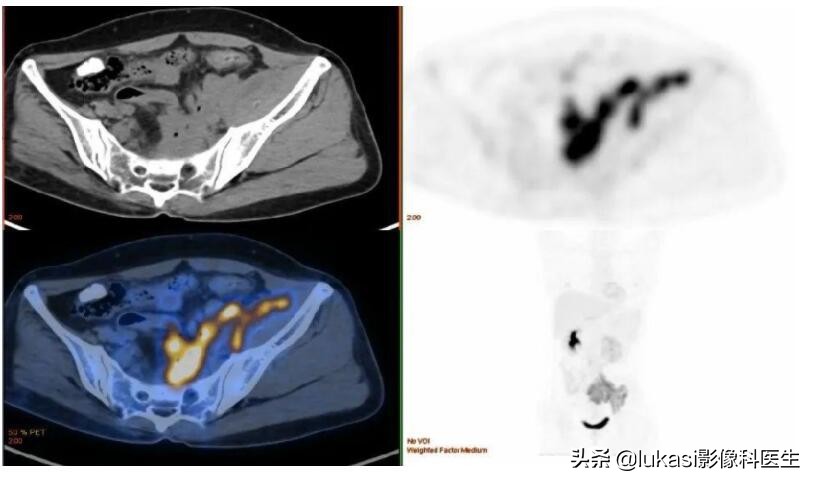

影像学检查: 如果诊断出宫颈癌(浸润癌),则进行盆腔检查和影像学检查(CT、MRI、PET 等),将癌症扩散到子宫周围的组织和淋巴结/其他器官。检查是否存在或无转移。基于这些结果,确定癌症的阶段。制定治疗对策。

宫颈癌PET-CT表现